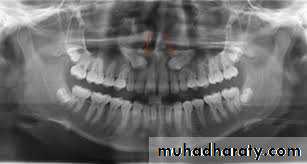

Periapical radiograph offers the highest definition and it should be used whenever possible, but the film should be positioned with care.

Orthopantomogram (OPG) is regarded as the radiograph of choice, its main advantages are; the low radiation exposure and its ability to demonstrate the entire dental arch.

Occlusal films are used in difficult cases especially in unerupted teeth in conjunction with another view at right angle, this is necessary to understand the problem in 3 dimensions.

Cone beam CT (CBCT) is relatively a new technique and it is indicated when on OPG there is a suggestion of a relationship between the roots of the impacted tooth and the inferior dental (alveolar) canal

Radiographic assessment

It aims to estimate how much work will need to be done at the operation and what technical difficulties will need to be overcome. The following features should be considered:• Angulation of the impacted tooth

• The depth of the impacted tooth, it can be assessed by Pell and Gregory classification, but other methods for depth assessment have been proposed.

• The relationship to the inferior dental canal, certain features may indicate the close proximity to the inferior dental canal; such as narrowing of the canal, loss of the continuity of the radio-opaque roof of the canal, overlapping, deflection of the canal or dilacerations of the roots.

• Crown features.

• Root morphology, e.g. fused roots, curved roots ...etc.• Bone density.

• Any associated pathology like cysts or tumors.

• The state of the second molar (root morphology, caries, restoration or resorption ...etc.)